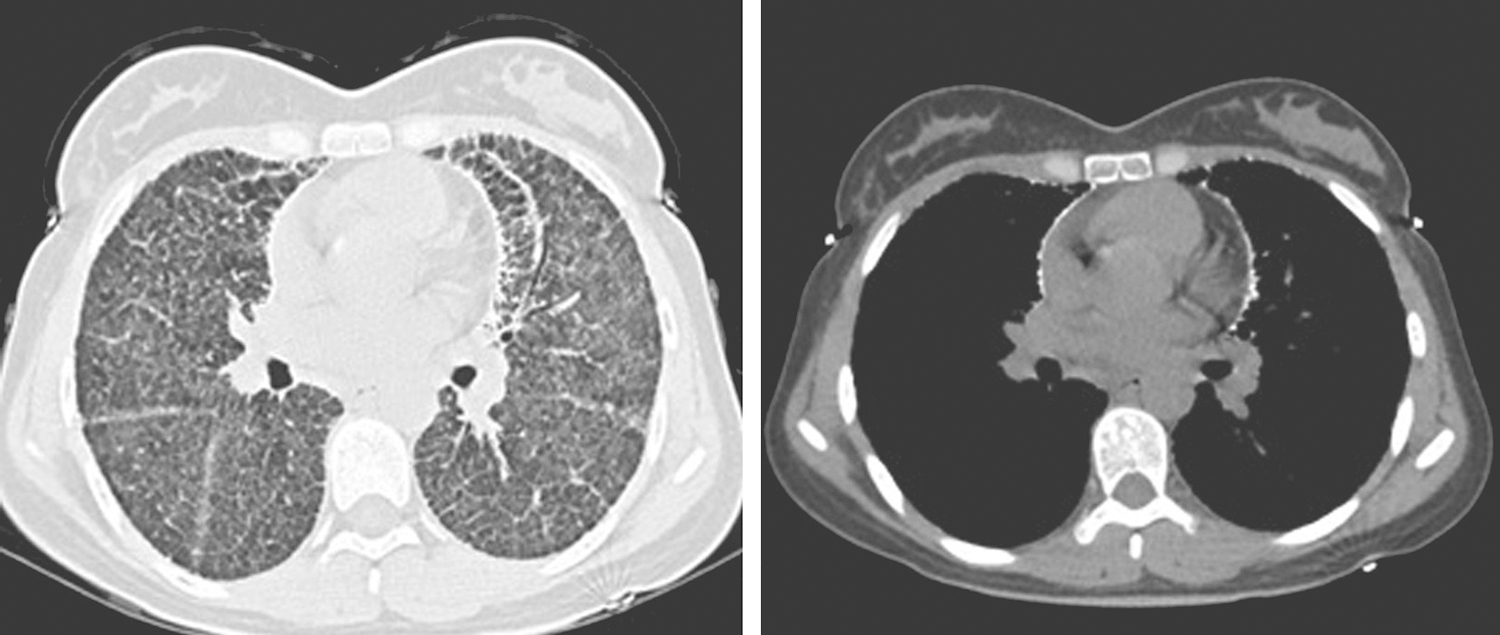

PAM的影像学特点是:早期胸片可见双肺有呈弥漫性散在分布的小颗粒样结节影,聚集于双侧中下肺叶及心包周围;胸部CT示对称性分布的细小粟粒状影、片状磨玻璃影及肺间质纤维化改变,双肺透亮度下降、胸膜增厚、胸膜及心包钙化等。细小粟粒状阴影随病变发展的程度不同而数目多少不等。早期易误诊,晚期纵隔窗可见“暴风雪”及“火焰征”样改变(图2)。

图2本研究患者肺部CT表现

目前认为胸部影像学检查是早期发现PAM的有效手段,尽管影像表现较有特征性,但仍需要与粟粒性结核、硅沉着病等类似影像表现的疾病相鉴别。